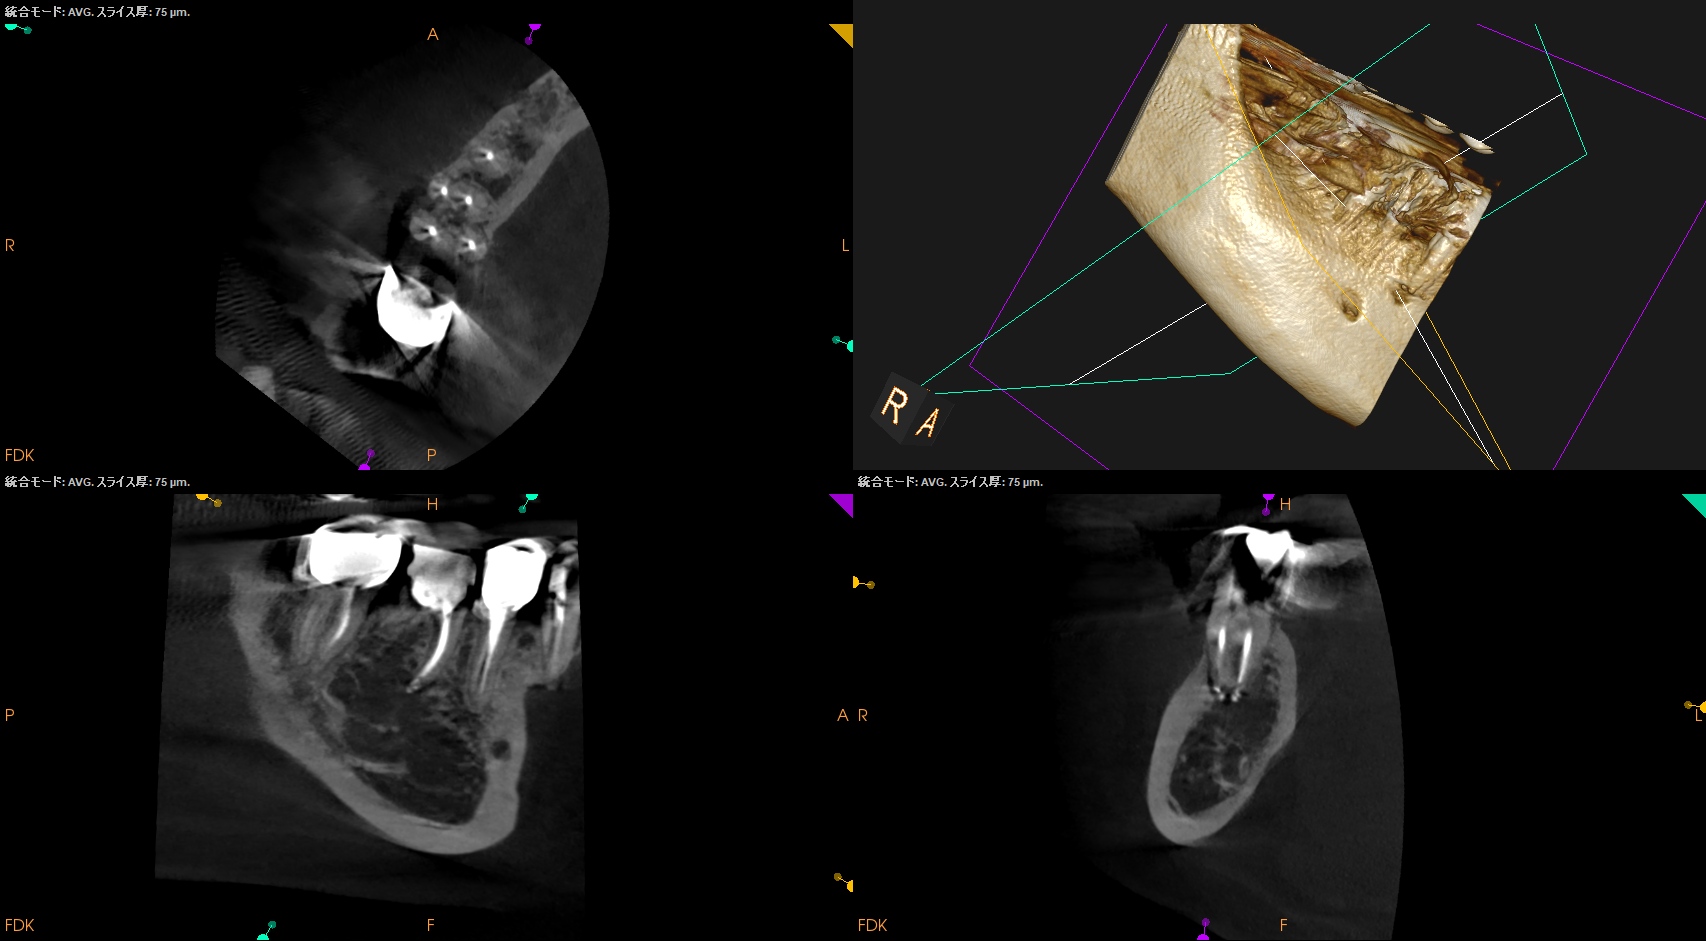

RadixはC Fileの#8で穿通している。

C Fileのテーパーは2なので0.5mm上部は#9である。

が、石灰化が極めて強くC Fileの#8をApexからさらに押し出す(突き出す)ことができなかった。

#6を使用したがこれもキツくApexから突き出せなかった。

このような場合(テーパー2度の#6,8が根尖から出せないくらい石灰化した根管の根管形成を行う場合)は、

HyFlex EDM #10.05を使用しなければならない。

今日はそれについて解説してみよう。

#10.05を2回通し、

#20.05を3回通し、

#25.Vも3回通し、

#40.04は1回だけ通している。